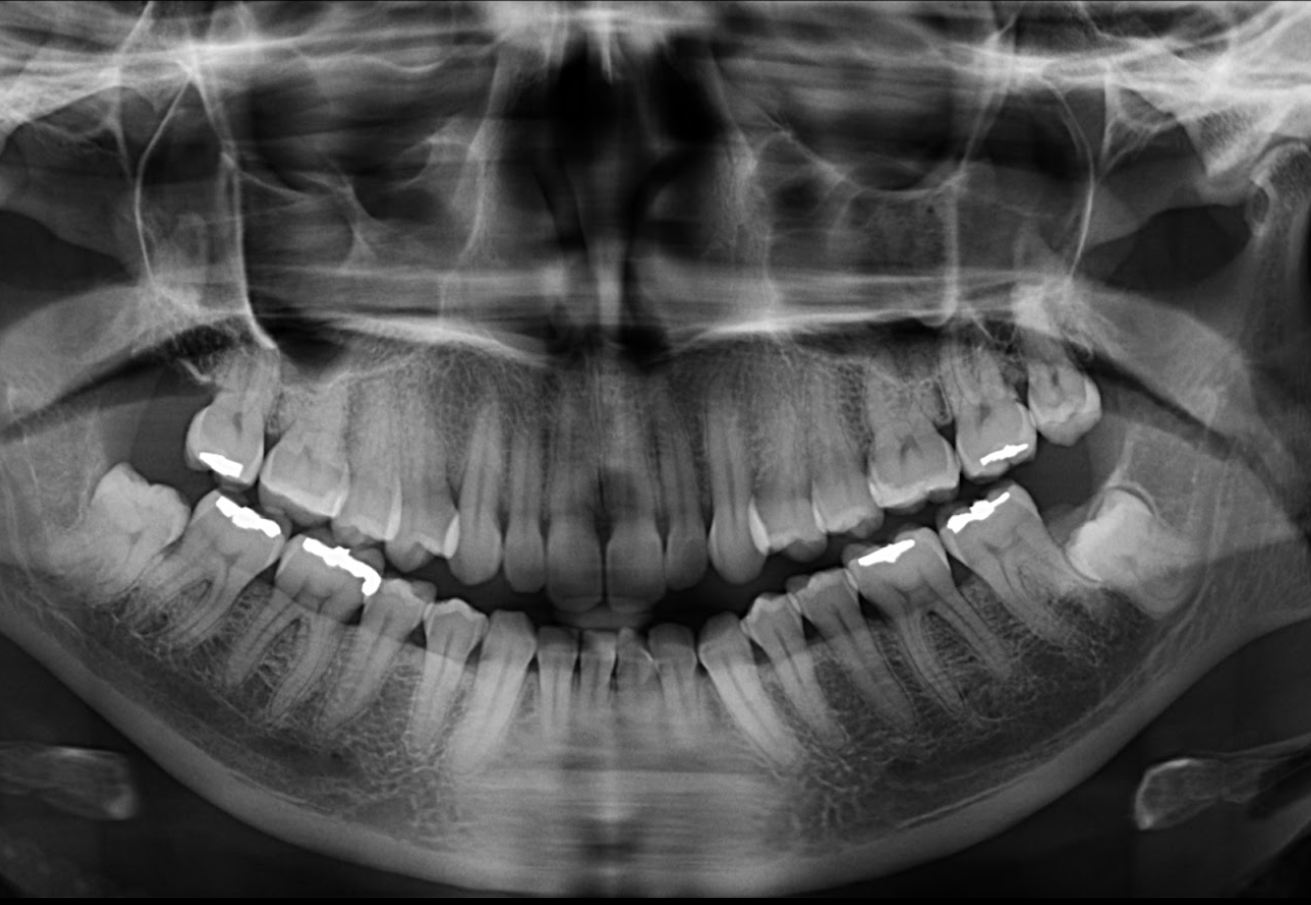

Paciente femenina acude a la sede de IDM- Miraflores para una tomografía computarizada para la evaluación de terceras molares. A la evaluación de la radiografía panorámica se observa aplanamiento del contorno condilar bilateral a predominio del lado derecho,

neumatización de ambos senos maxilares, múltiples restauraciones coronarias, ausencia de la pieza 18 y la impactación de la pieza 38 que a su vez presenta dilaceración de la raíz mesial e hipercementosis.

A la evaluación de la tomografía computarizada del motivo de consulta que fue la pieza 48 se observa impactada contra la superficie cervicodistal de la pieza 47, asimismo se observa la presencia de una raíz supernumeraria por vestibular y por mesial (paramolaris), la

hipercementosis de los tres segmentos, así como la dilaceración de los mismos a predominio de la raíz supernumeraria. Finalmente, el conducto dentario inferior recorre por lingual de la raíz distal y por el medio de ambas raíces mesiales, contactando con los ápices.